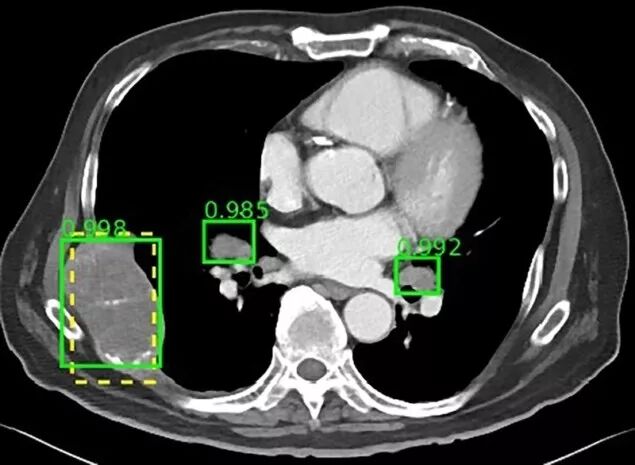

该数据库包括来自马里兰州贝塞斯达NIH临床中心的4400多名患者的大约10600项研究。虽然目前大多数数据库包含10至数百个单一类型的病变,但该组设计的DeepLesion可容纳超过32000个病灶,涵盖各种放射学发现,如肺结节、淋巴结肿大和肝肿瘤。

有了多范畴的病变数据库,DeepLesion为研究人员提供了开发人工智能算法的机会,能够自动检测和诊断多种病变类型。美国国立卫生研究院指出,未来它还可能发展成为一个通用病变检测器,可用作初始筛选工具,并将其结果发送到其他更专业的算法。此外,研究人员可能可以在同一次CT扫描中研究不同类型病变之间的关系,从而全面评估癌症负担。

为了开始展示这种潜力,Summers及其同事用DeepLesion数据库来训练一个典型的通用病变检测器,以发现各种病变。他们的探测器灵敏度达到81.1%,每个图像有5个假阳性。